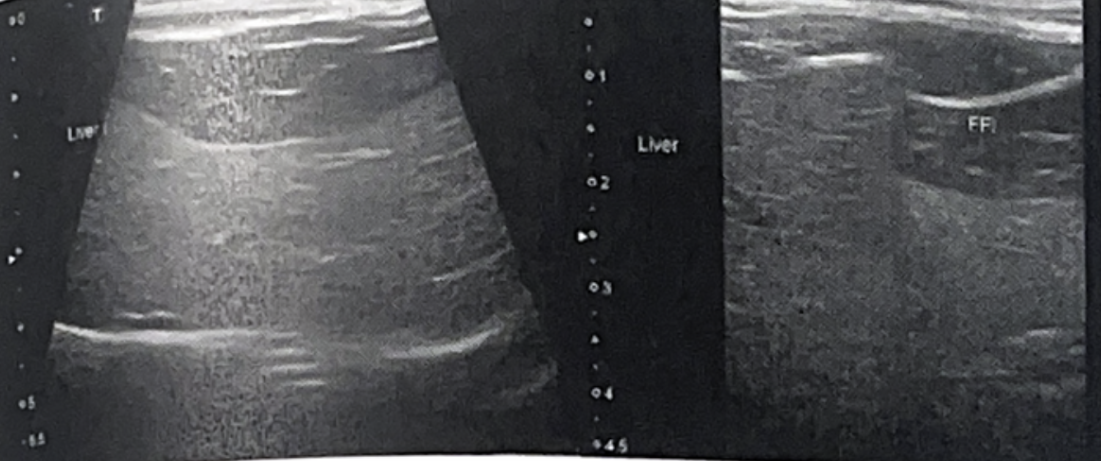

- Hepatomegaly & fine echotexture, hyperechoic

- Attenuation 소견은 당뇨에서 가장 심하게 나타남

✴️ Hepatic lipidosis

- Hyperechoic해짐 (falciform fat보다)